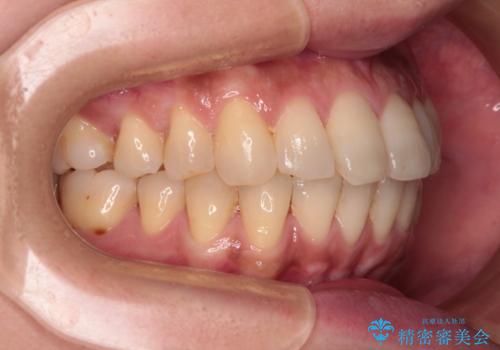

インビザラインによる矯正治療と奥歯のインプラント治療

- 全体的なデコボコと、以前抜歯した歯のスペースを閉じた部分が気になるとのことで来院された患者様です。

左上第一大臼歯を抜歯した際に、スペースを閉じたそうですが、歯が傾斜してものが挟まって不快とのことでした。

インビザライン矯正で全体の歯列と整えるとともに、左上第一大臼歯部にはスペースを作り、インプラントによる補綴治療を行うこととしました。

歯の傾斜が改善され、インプラントによるクラウンが装着されたことで、物が挟まることもなくなりました。